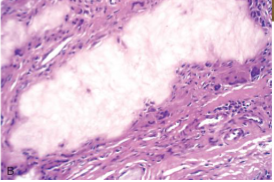

Rheumatoid nodules

Subcutaneous Rheumatoid nodules

Rheumatoid Arthritis

Immune Complex activation of Macrophages

Occur in mostly “pressure areas” such as elbows, ulnar forearm, lumbosacral region, or periarticular; less commonly in visceral organs

Firm, freely moveable, nontender

more frequent in those with severe disease

Histology: palisaded granuloma with central fibrinoid necrosis